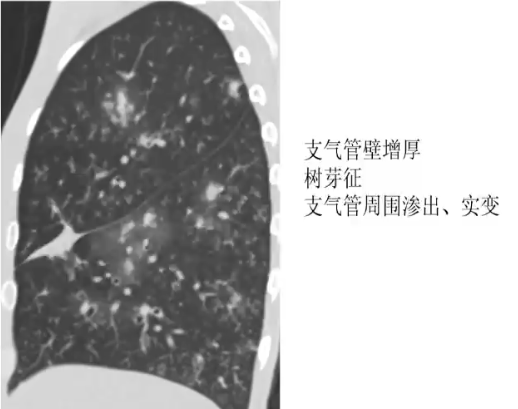

❖ 急性气管支气管炎表现

❖ CT表现:气管、支气管壁增厚,支气管炎(小叶中心结节和树芽征)、支气管肺炎(肺门旁分布为主的实变)